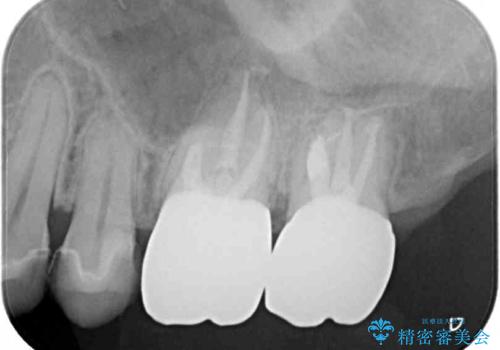

根管治療後、病変が消退したことを確認し、オールセラミッククラウンにて補綴治療を行うこととしました。

2,3回の処置後には来院時に感じていた痛みはなくなり、根管治療から半年後にはレントゲンでの根尖部病変も消失していました。